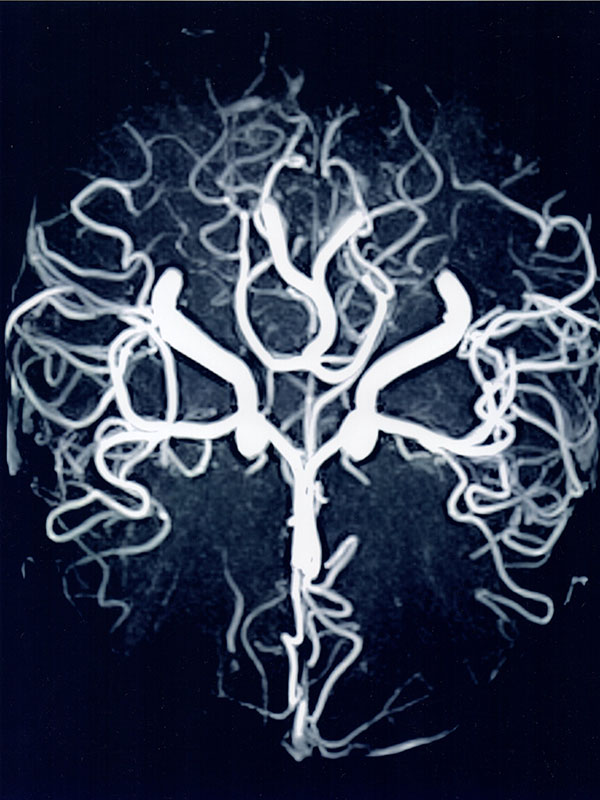

Se realizan todos los estudios solicitados habitualmente como ser de cráneo y sus distintos sectores sin y con contraste, estudios de hipófisis, oído, nervios craneales, estudios de “Angio-resonancia” para analizar tanto las arterias como las venas del cerebro, entre otros.

- “Angio-resonancia” de alta resolución para analizar las arterias y las venas del cerebro